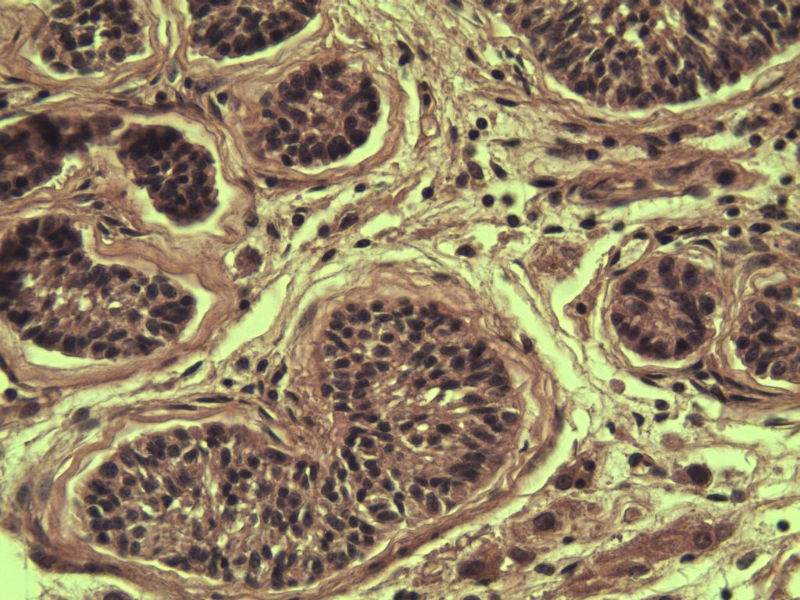

腹腔隐睾图2

名称:图2

描述:a211.Jpg.jpg